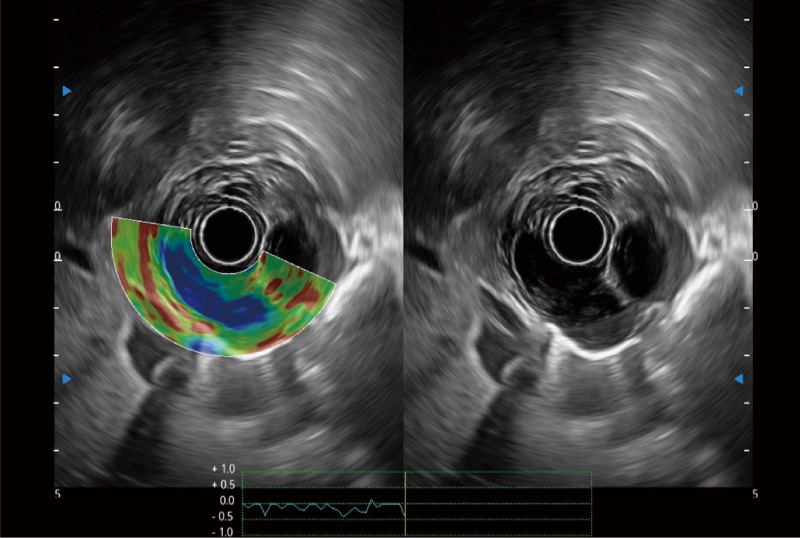

可人為將灰階圖像轉(zhuǎn)變成彩色的顯示方式,增強(qiáng)人眼對(duì)于不同回聲強(qiáng)度的敏感度,主觀上增加了圖像分辨率

位移矯正技術(shù)

不可靠區(qū)域自動(dòng)剔除

彈性定量分析軟件